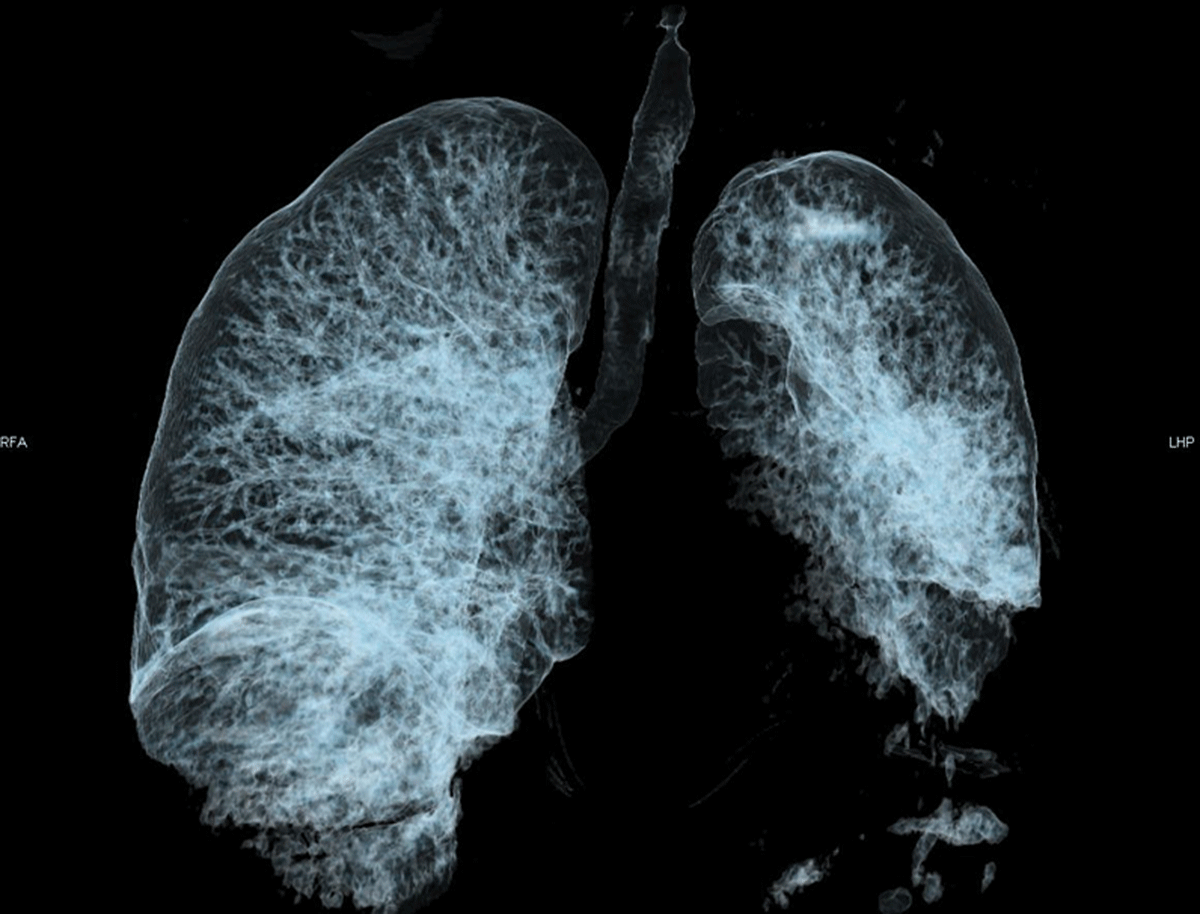

Figure 1

Volume rendering 3D reformat of the airways showing complete obstruction of the non-visible left mainstem bronchus. The air visible in the left lung results from the aerated collapse of the left upper lobe. The left lower lobe suffered non-aerated collapse and thus is not visible.